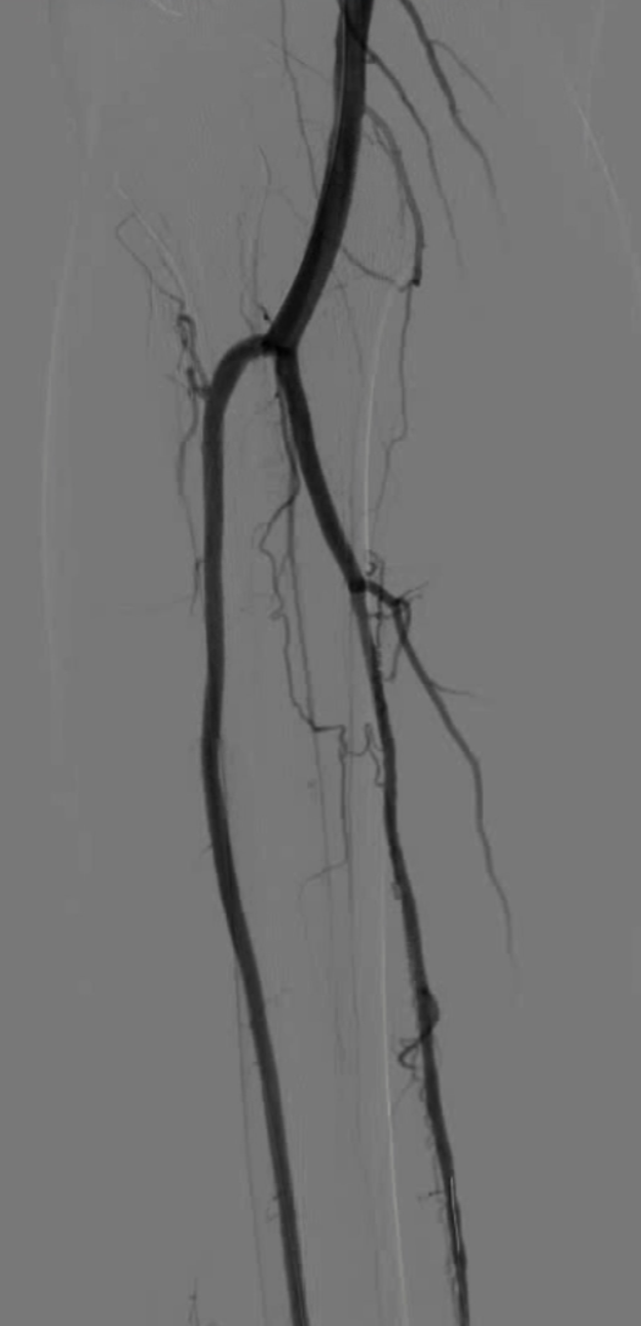

TAO动脉病变模式有 abrupt occlusion(突然闭塞)、Localized stenosis(局限性狭窄)、Moth-eaten stenosis(虫蚀样狭窄)等,还可能出现不规则侧支循环、侧支循环早期形成、树根样侧支、迂曲静脉等情况。

血管内治疗成为主要选择,尤其对于无远端旁路靶点患者

48岁男性,右足溃疡反复发作,多次PTA+DCB治疗

2023.3 右足部溃疡2个月,行PTA

2024.5,再发溃疡4个月,先后两次PTA

2024.9,溃疡未愈合,胫前动脉、胫后动脉PTA+DCB